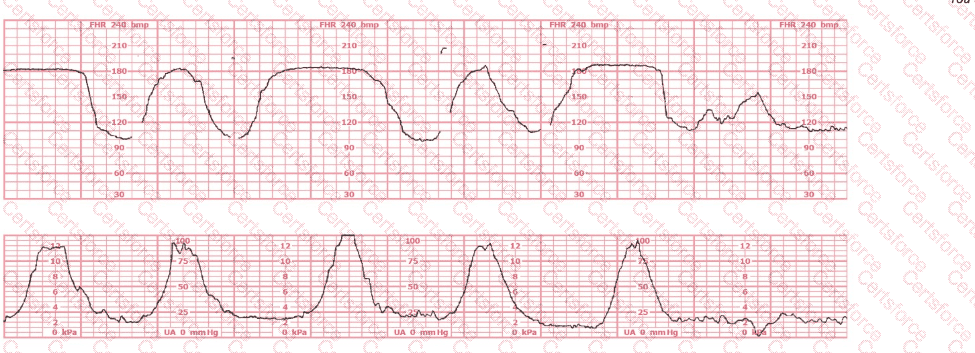

Questions # 7:

This fetal heart rate pattern is classified as Category III based on:

Question # 7

A.

B.

C.